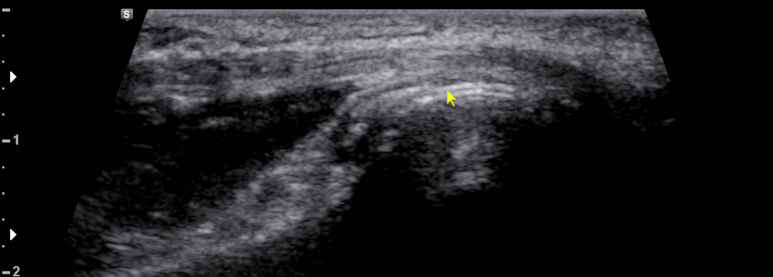

환부 관절의 연골면에 고음영의 요산 침착이 관찰됨 (double contour sign)

관절에 통풍결절이 관찰됨